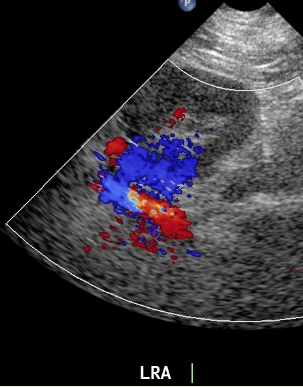

The last, but perhaps most important, part of performing the renal artery ultrasound from the flank approach is to sample the renal artery. The goal of the ultrasonographer is to elongate as much as the renal artery from the hilum to the aorta. If the full length of the renal artery is identified, then velocity sampling can be performed with confidence. Otherwise, there is an element of guessing.

Tip: Usually, elongating the renal artery requires showing the kidney in transverse. This is termed a “C” image, because the kidney assumes a shape of the letter “C”. The hilum and renal artery exit the “C” toward the aorta.

Sampling from the renal artery should be performed with angle correction.